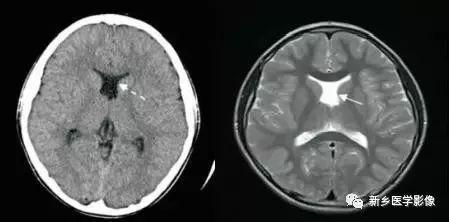

8.胼胝体发育不良

在脑发育腹侧诱导晚期,新形成的端脑嘴侧壁的背侧部分增厚、内陷,向后沿尚未完全发育的大脑半球间裂延伸。两个月后形成一个连合即胼胝体纤维的细胞框架,该细胞框架形成后胼胝体相应部分立即发育。膝部先发育。然后是体部、压部.位于胼胝体膝部后下方的胼胝体嘴最后发育。如果胼胝体发育过程中出现有害因素,就有可能导致胼胝体发育不良.表现为完全缺如或部分缺失。常表现为膝部存在或膝部和体部存在。压部和胼胝体嘴缺失。

胼胝体发育不良可见单独发病,但更常见的是伴有中枢伸经系统的其他畸形,包括胼胝体周围脂肪瘤、脑膨出、交通性脑积水Chaiarii畸形、Dandy-Walker囊肿、脑裂畸形等。临床上可无症状或仅有轻度临床症状,临床检查可见眼距过宽、大头畸形、智力发育迟滞等。胼胝体缺失时,MR冠状位上侧脑室前角呈新月形表现,侧脑室体部分离,呈垂直状平行走行。